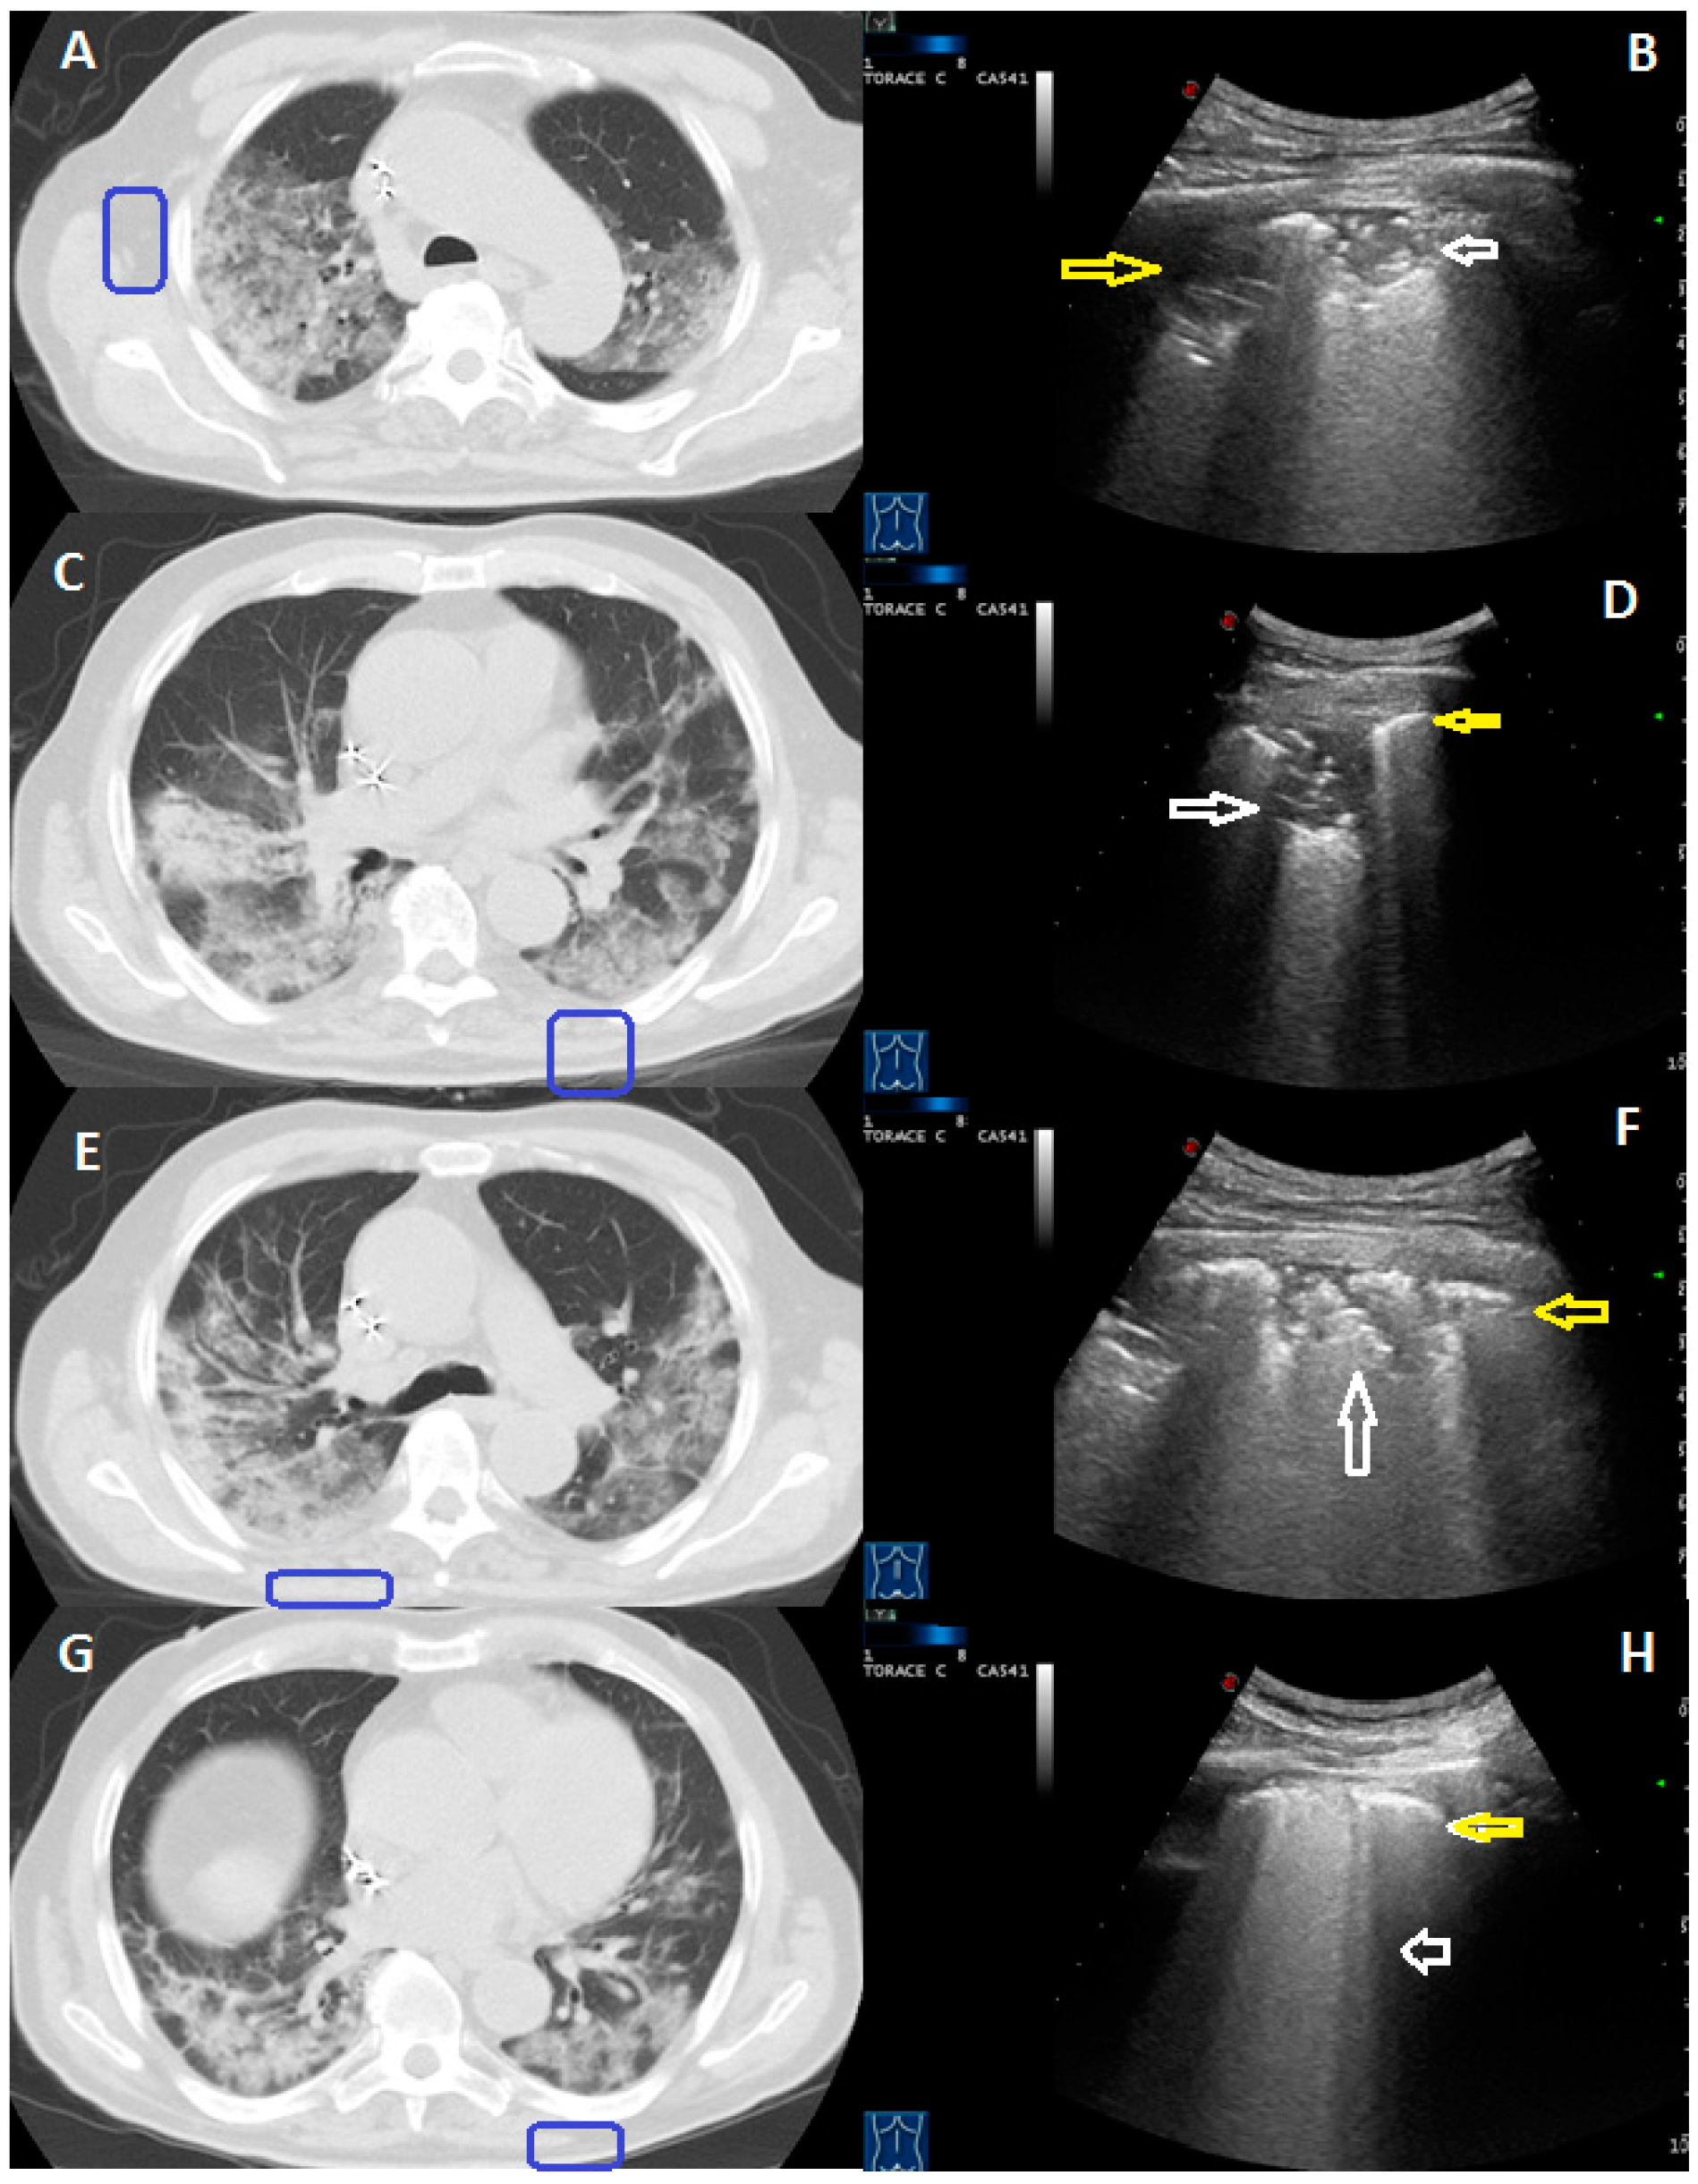

- The Chest-CT crazy pattern of bilateral, patchy, or extensive peripheral GGOs associated with smooth interlobular and intralobular septal thickening was identified at LUS in a total 30/58 patients (52%), with an echographic pattern consisting in a blurred and thickened hyperechoic pleural line, with or without associated subpleural hypoechoic lung striae, and B-lines below the pleural line (Figure 1).